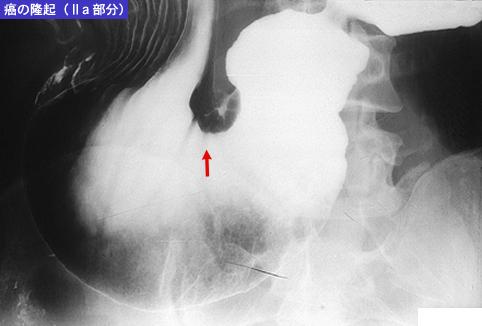

Criteria of Hist.ClassificationMalignant epithelial tumor/Signet-ring cellcarcinoma

LocationStomach/Angle

Technique, MethodX-ray

Macroscopic TypesType 0/IIc (IIc+IIa) Superficial depressed and elevated type

Size40 -

Depth of Tumor Invasionsubmucosa